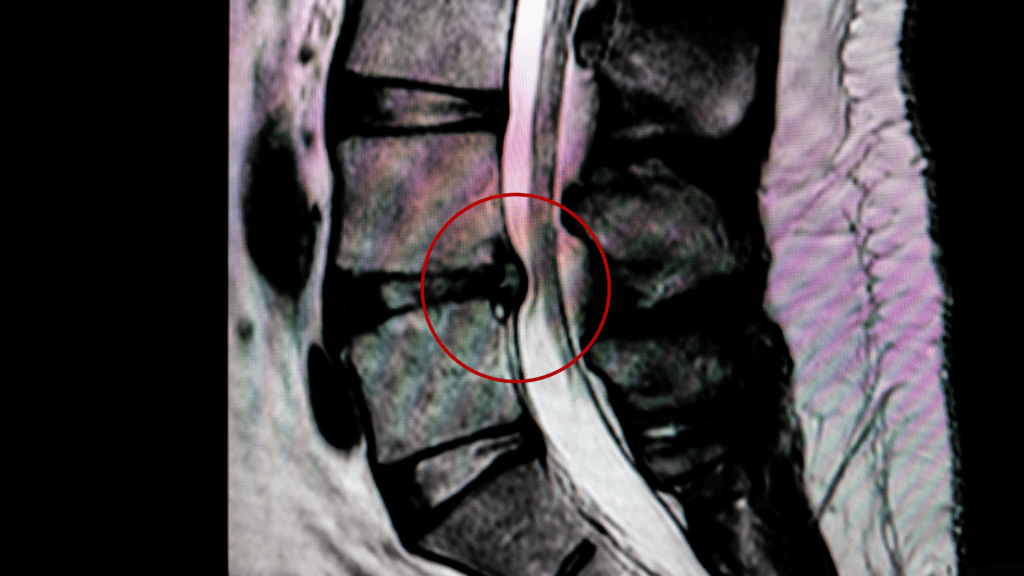

Disc-Related Conditions

Lumbar disc bulges, herniations, or degenerative disc changes may place pressure on nerve roots that form the sciatic nerve, leading to radiating leg pain.